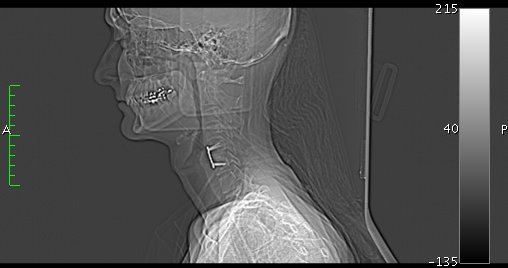

When I look left, my left arm goes numb. So they sent me in for more scans. I learned first-hand that MRIs induce electrical currents in titanium, which can be quite interesting when it's pointing at your spinal cord. Some minor findings, but nothing major warranting more surgery. Which is good. As long as I don't need to look left.

Here's a movie (30MB) we made from the CT data with which to entertain you. Please enjoy it with much glee so when I die of thyroid or brain cancer I'll know deep down it was all worthwhile. Click on the image to view or download. (It's just a 360 rotation, alas. Sorry, no singing skulls.)